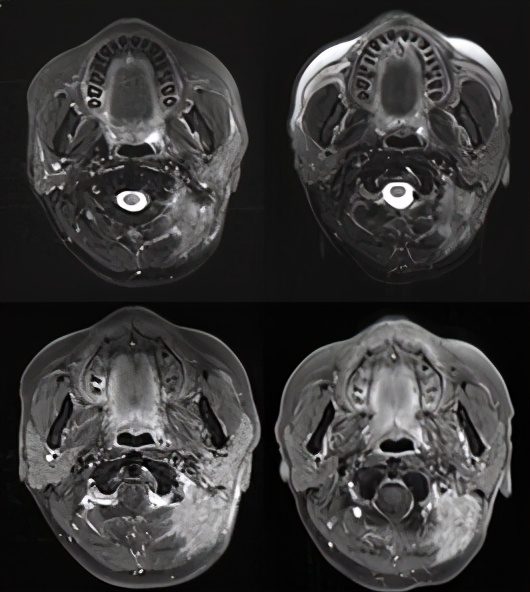

德瓦鲁单抗联合化疗第一次影像评价(左:治疗前;右:治疗后2020.5.11)